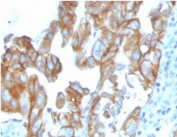

IHC staining of FFPE human colon carcinoma tissue with MERTK antibody (clone MERTK/3023). HIER: boil tissue sections in pH 9 10mM Tris with 1mM EDTA for 20 min and allow to cool before testing.